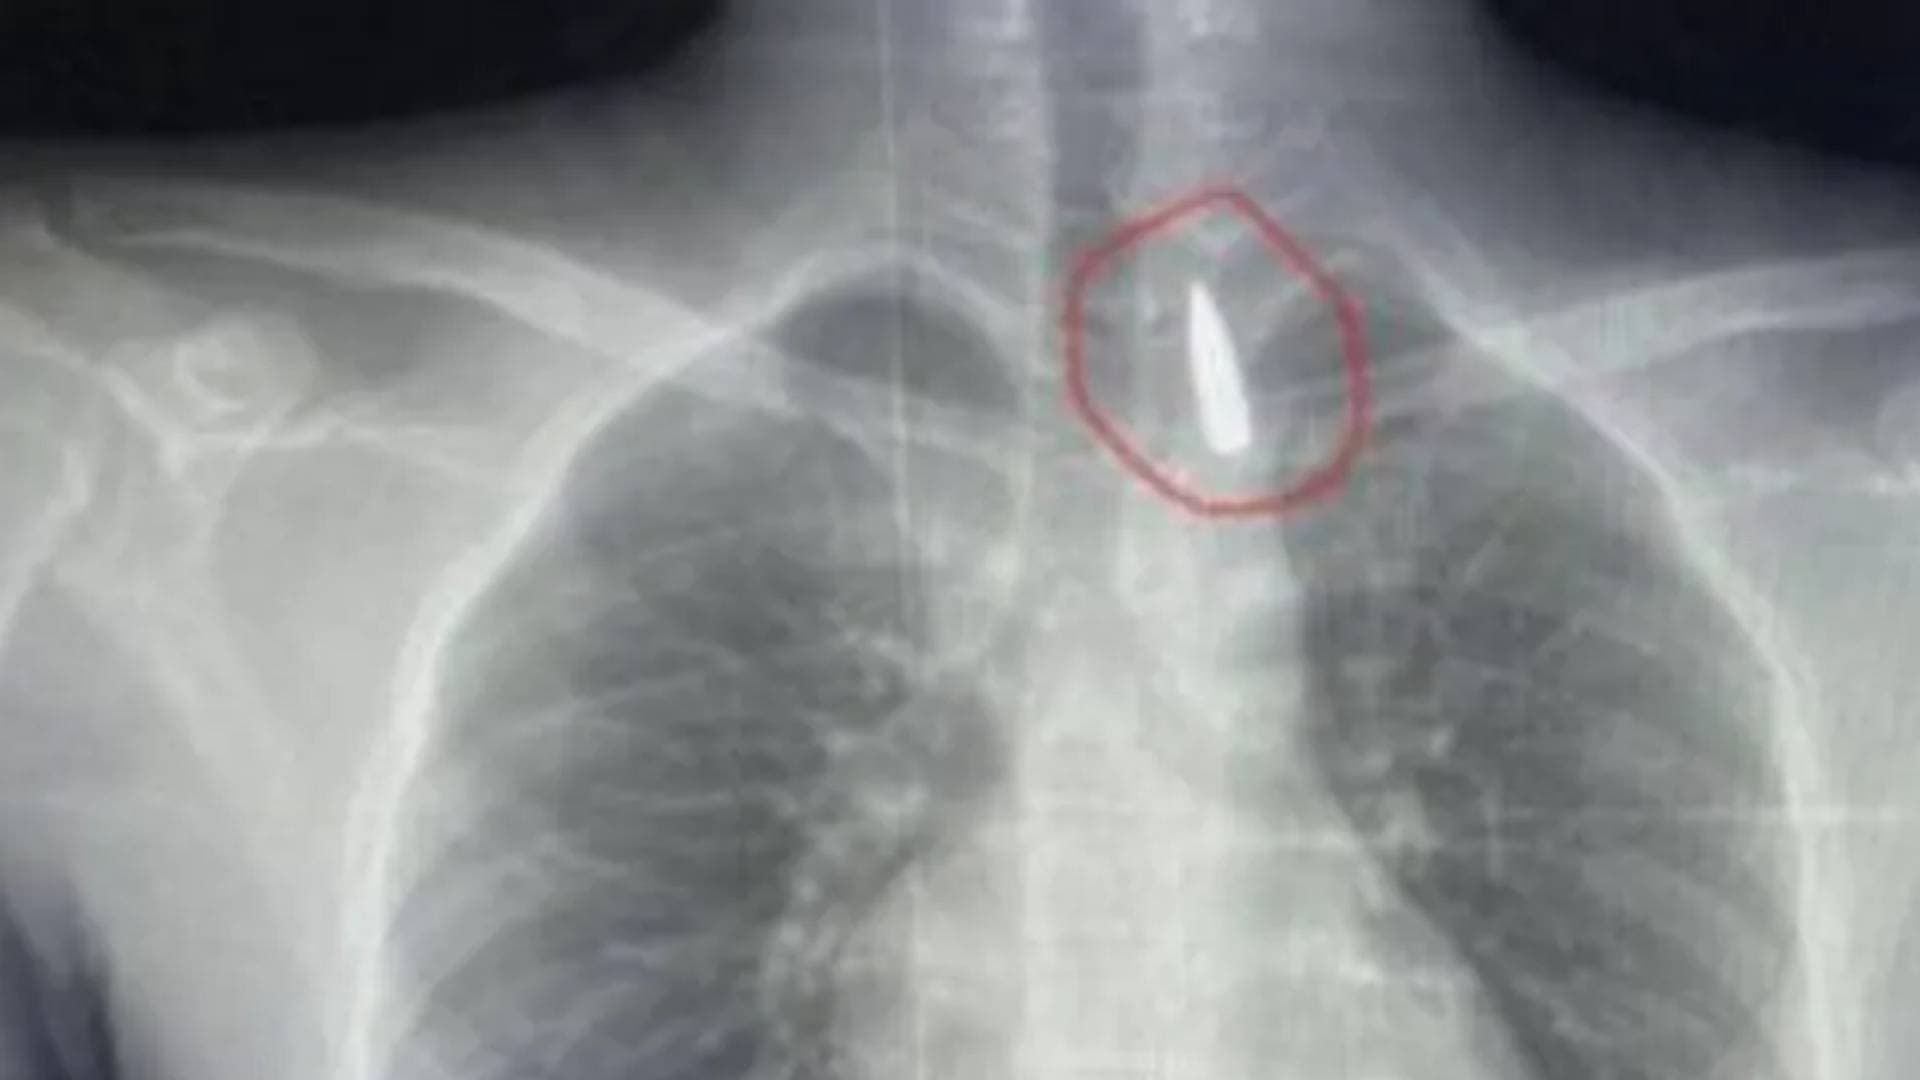

وأوضح عمر العوفى ، أن جراحة الكتف أن التفوق في تخصص العظام هو التزام يومي تجاه المريض، وليس مجرد خبرة تكتسب مع مرور الوقت، لافتا إلى أن جراحة الكتف تعد من أكثر التخصصات دقة وتعقيدا نظرا لتداخل المفاصل والعضلات والأوتار، ما يتطلب تشخيصا دقيقا وخطة علاجية متكاملة تبنى على أسس علمية واضحة.

وأشار إلى أن التعامل مع الحالات الصعبة يستوجب رؤية شمولية تبدأ من التشخيص المبكر والدقيق، مرورا باختيار التقنية الجراحية الأنسب، وانتهاء ببرامج تأهيل مصممة خصيصا لكل مريض، بهدف استعادة الحركة الطبيعية وتحسين جودة الحياة.